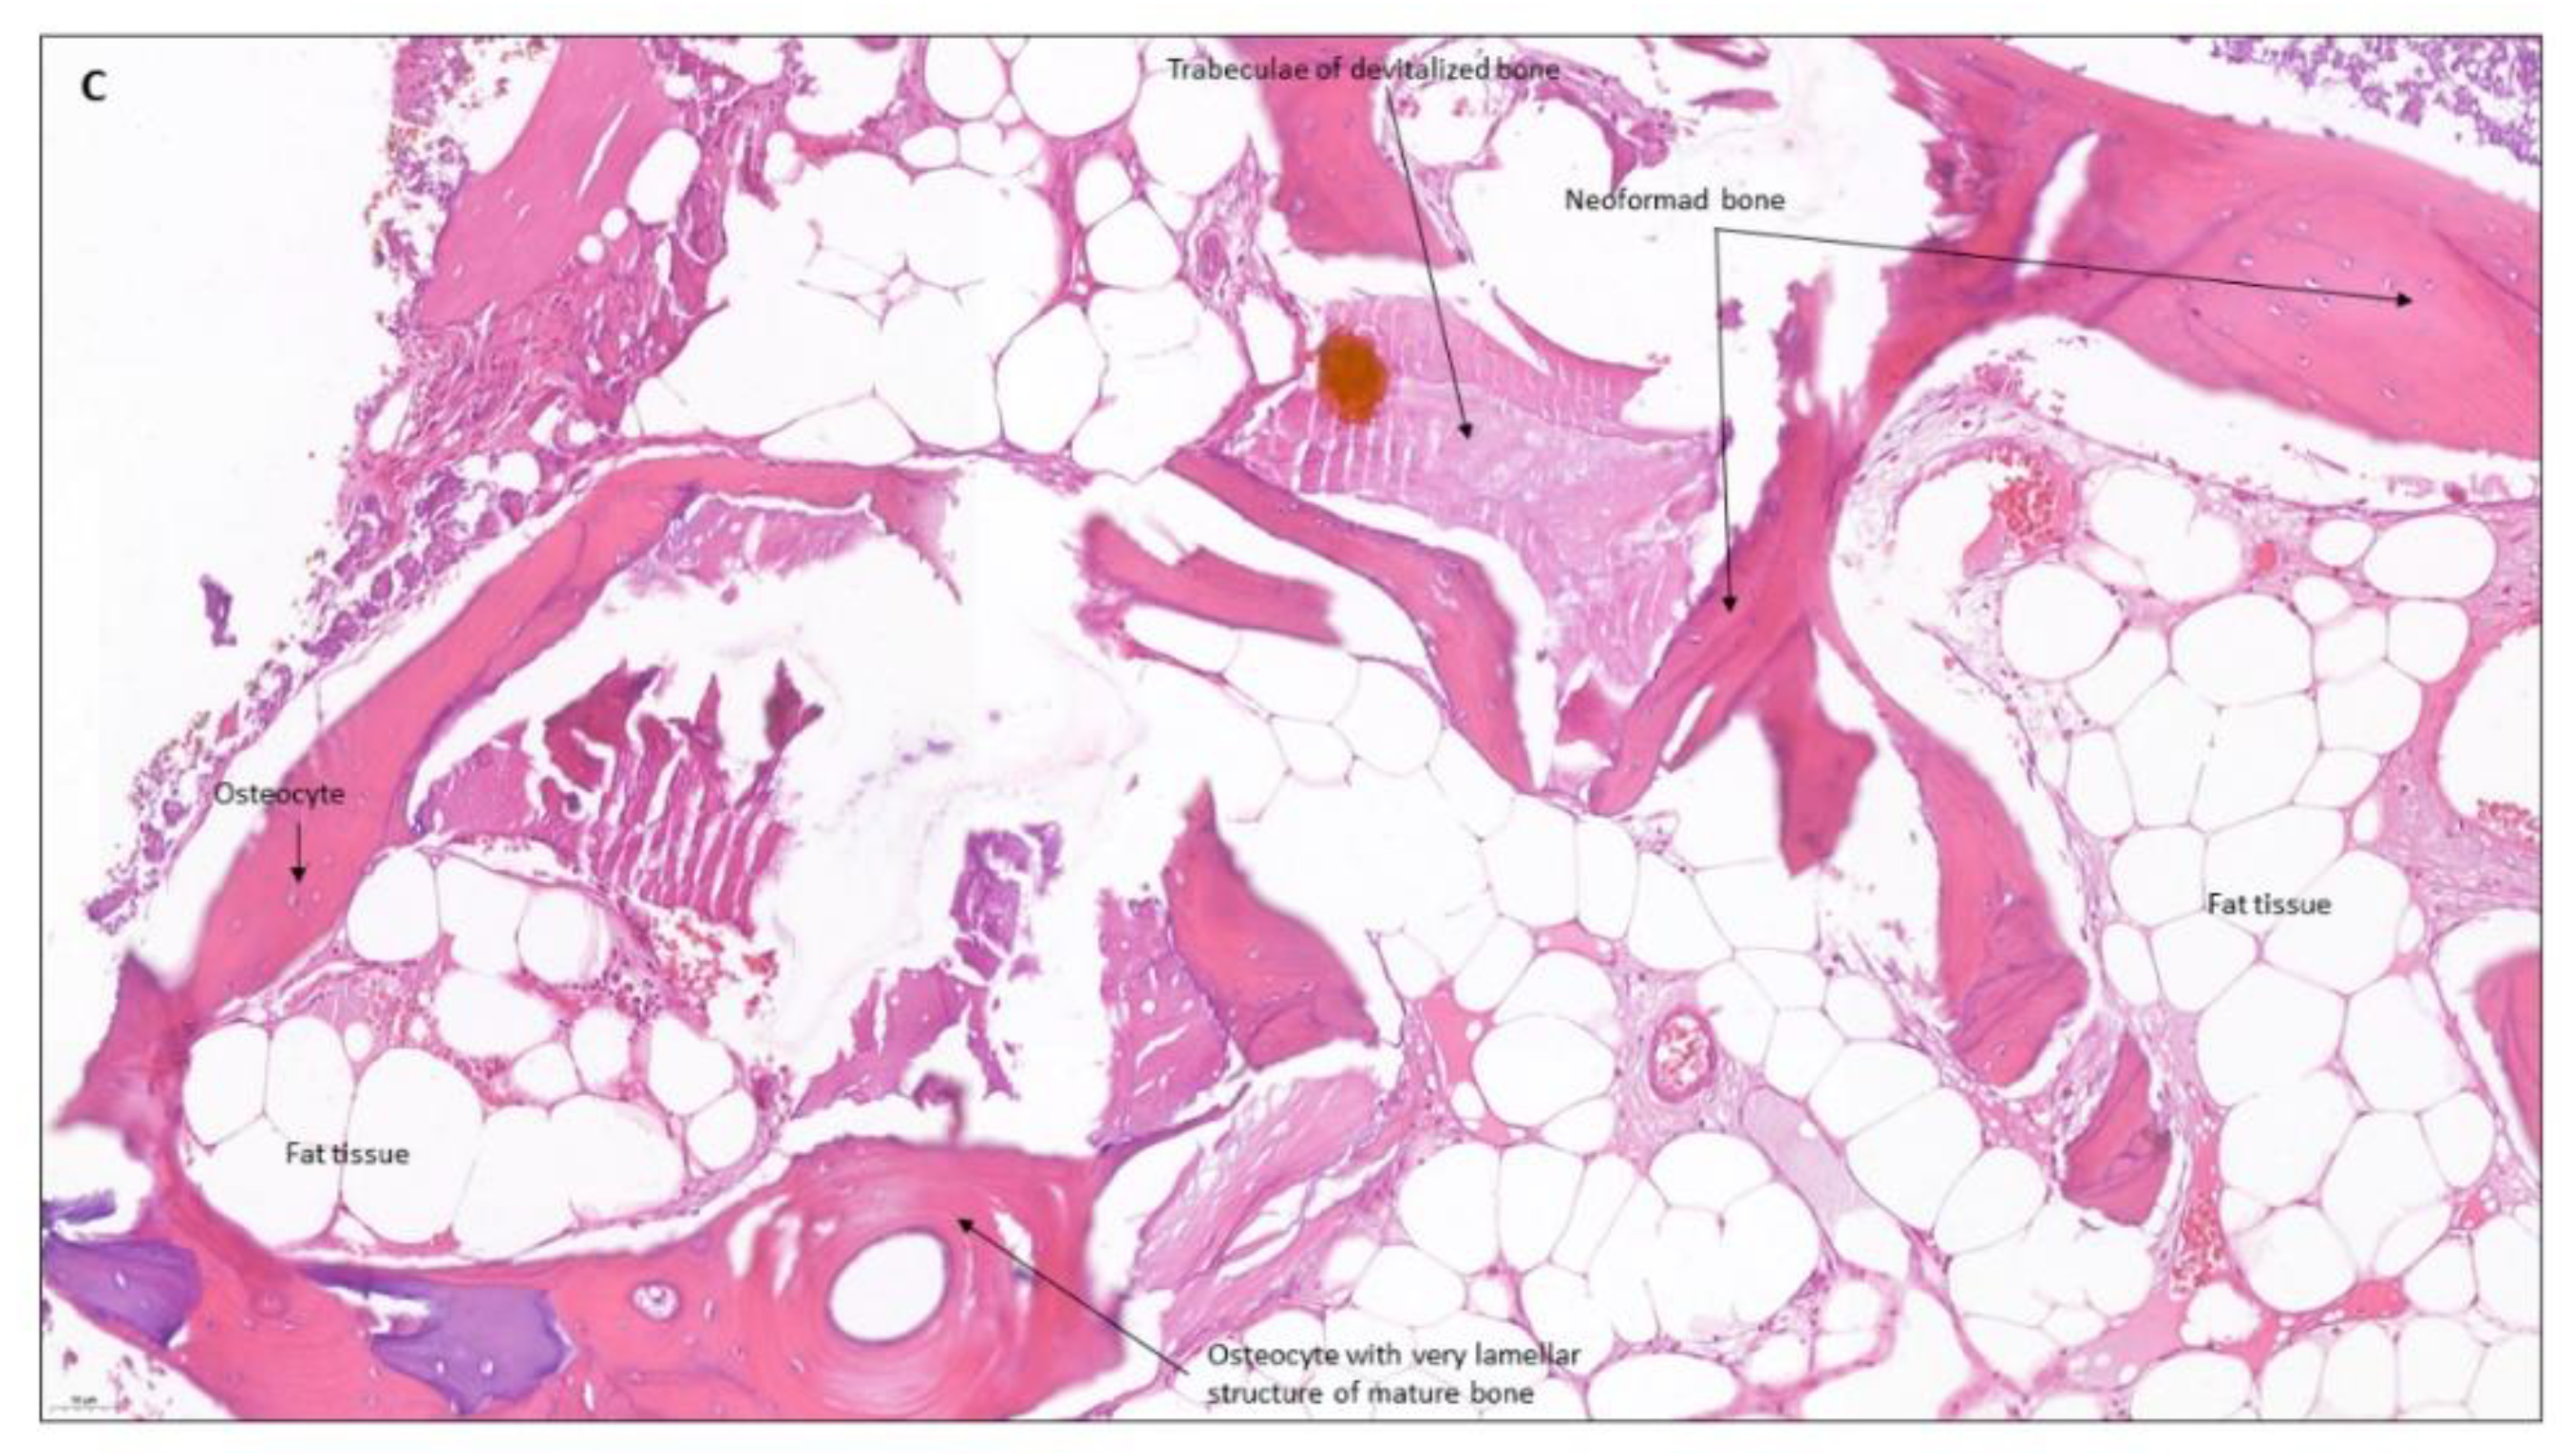

4. Clinical Cases

4.1. Patient No. 1

4.2. Patient No. 2

4.3. Patient No. 3

4.4. Patient No.4

4.5. Patient No.5

4.6. Patient No.6

| Machtei et al. [30] 2018 RCT | n: 11 7M/4F 45–80 = 64 years old | To compare the dimensional changes and bone quality of calcium sulfate (BCS/HA) and bovine xenograft (BDX) in socket preservation cases. | At 4 months Bone height loss: BDX 0.25 mm, BCS/HA 0.65 mm, Control 1.7 mmBone width loss at −3 mm: BDX 1.56 ± 0.4 mm, BCS/HA 0.5 ± 0.4 mm Control 2.96 ± 0.3 mmNew bone formation: BDX 21,5%, BCS/HA 44.4% y Control 81,5%. Remaining graft material: BDX 44.18%, BCS/HA 16.51%. | Calcium sulfate can be used as the material of choice for socket preservation with similar and sometimes even better results than bovine xenograft. | |

| Mayer et al. [31] 2016 RCT | n: 36 13M/23F Splitmouth CS n: 14, Control n:15 | To evaluate the efficacy of calcium sulfate in cases of socket preservation. | At 4 months Bone height loss: CS 0.3 ± 2.01, Control 0.1 ± 2.03 Bone width loss at −3 mm: CS 0.03 ± 2.32 mm, Control 2.28 ± 2.36 mm Histopathological analysis: CS 47.7% bone, 36.3% connective tissue graft y 16% remaining graft material Control 52.6% bone y 46.7% connective tissue graft | Calcium sulfate is an effective material in socket preservation cases, providing better results than natural healing. | |

| Horowitz et al. [32] 2012 Case series | n: 40 | To evaluate the efficacy of calcium sulfate in cases of socket preservation. | At 4 months Bone volume and density were maintained. Calcium sulfate is completely reabsorbed, giving rise to new bone. | Calcium sulfate is an effective material in cases of socket preservation before implant placement. | |

| Dudek et al. [33] 2020 CT | CS n: 30 14M/16F 28–68 = 55.6 years old | Xenograft n: 30 14M/16F 27–65 = 61.1 years old | To evaluate the efficacy of calcium sulfate in the regeneration of maxillary bone defects after surgical removal of radicular cysts compared to the use of xenografts. | Calcium sulfate achieves faster bone remodeling than bovine xenograft. Virtually complete reabsorption of calcium sulfate and replacement by new bone at 3 months. | The use of calcium sulfate proved to be a simple, inexpensive, and effective reconstructive treatment of bone defects after the enucleation of odontogenic cysts. |